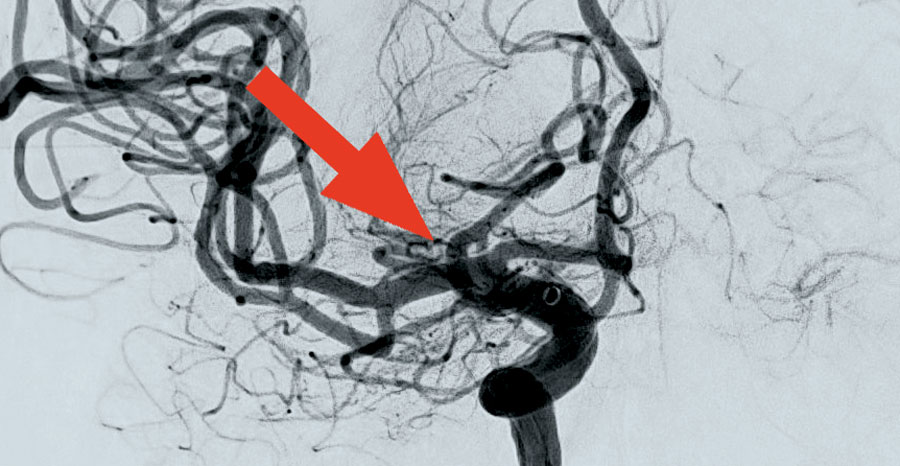

Wie kann man sich so einen Eingriff mittels Angiografie vorstellen? Vereinfacht gesagt: Mit Kathetern wird über die rechte Leiste der Weg über die Beckenarterien und die Aorta bis zum Aortenbogen und von dort über die Hals- oder Wirbelsäulenschlagader bis in die Hirnbasisarterien gegangen. Mit dem Röntgen-Durchleuchtungsgerät – für Spezialisten: eine biplane Flachdetektor 3D-Rotationsangiografie Azurion – lässt sich das bestens am großen Monitor über dem Behandlungstisch verfolgen und steuern. Ist das Blutgerinnsel erreicht, wird darüber ein sogenannter Stent-Retriever eingebracht. Dieser soll sich mit seinen Maschen in das Blutgerinnsel „hineinfressen“. Das „gefangene“ Blutgerinnsel wird dann mit dem Stent-Retriever zurückgezogen. Über einen zusätzlichen Katheter wird ein Sog erzeugt, der die gelösten Blutgerinnselanteile aus der Arterie „heraussaugt“.

Voraussetzung für die Behandlung eines Schlaganfalls ist, dass es sich nicht um einen „manifesten Infarkt“ handelt. Sprich, dass also bestimmte Regionen des Gehirns nicht schon zu lange unterversorgt waren. Einer der ersten Fälle für Dr. Johannes Waidelich war gleich ein eher ungewöhnlicher: 97 Jahre alt war die Patientin, allerdings als Selbstversorgerin und ohne relevante Vorerkrankungen noch sehr gut aufgestellt war. Schon 40 Minuten nach Eintreffen der Dame konnte Dr. Waidelich mit der Behandlung beginnen und erfolgreich ein Blutgerinnsel aus der mittleren Hirnschlagader entfernen.